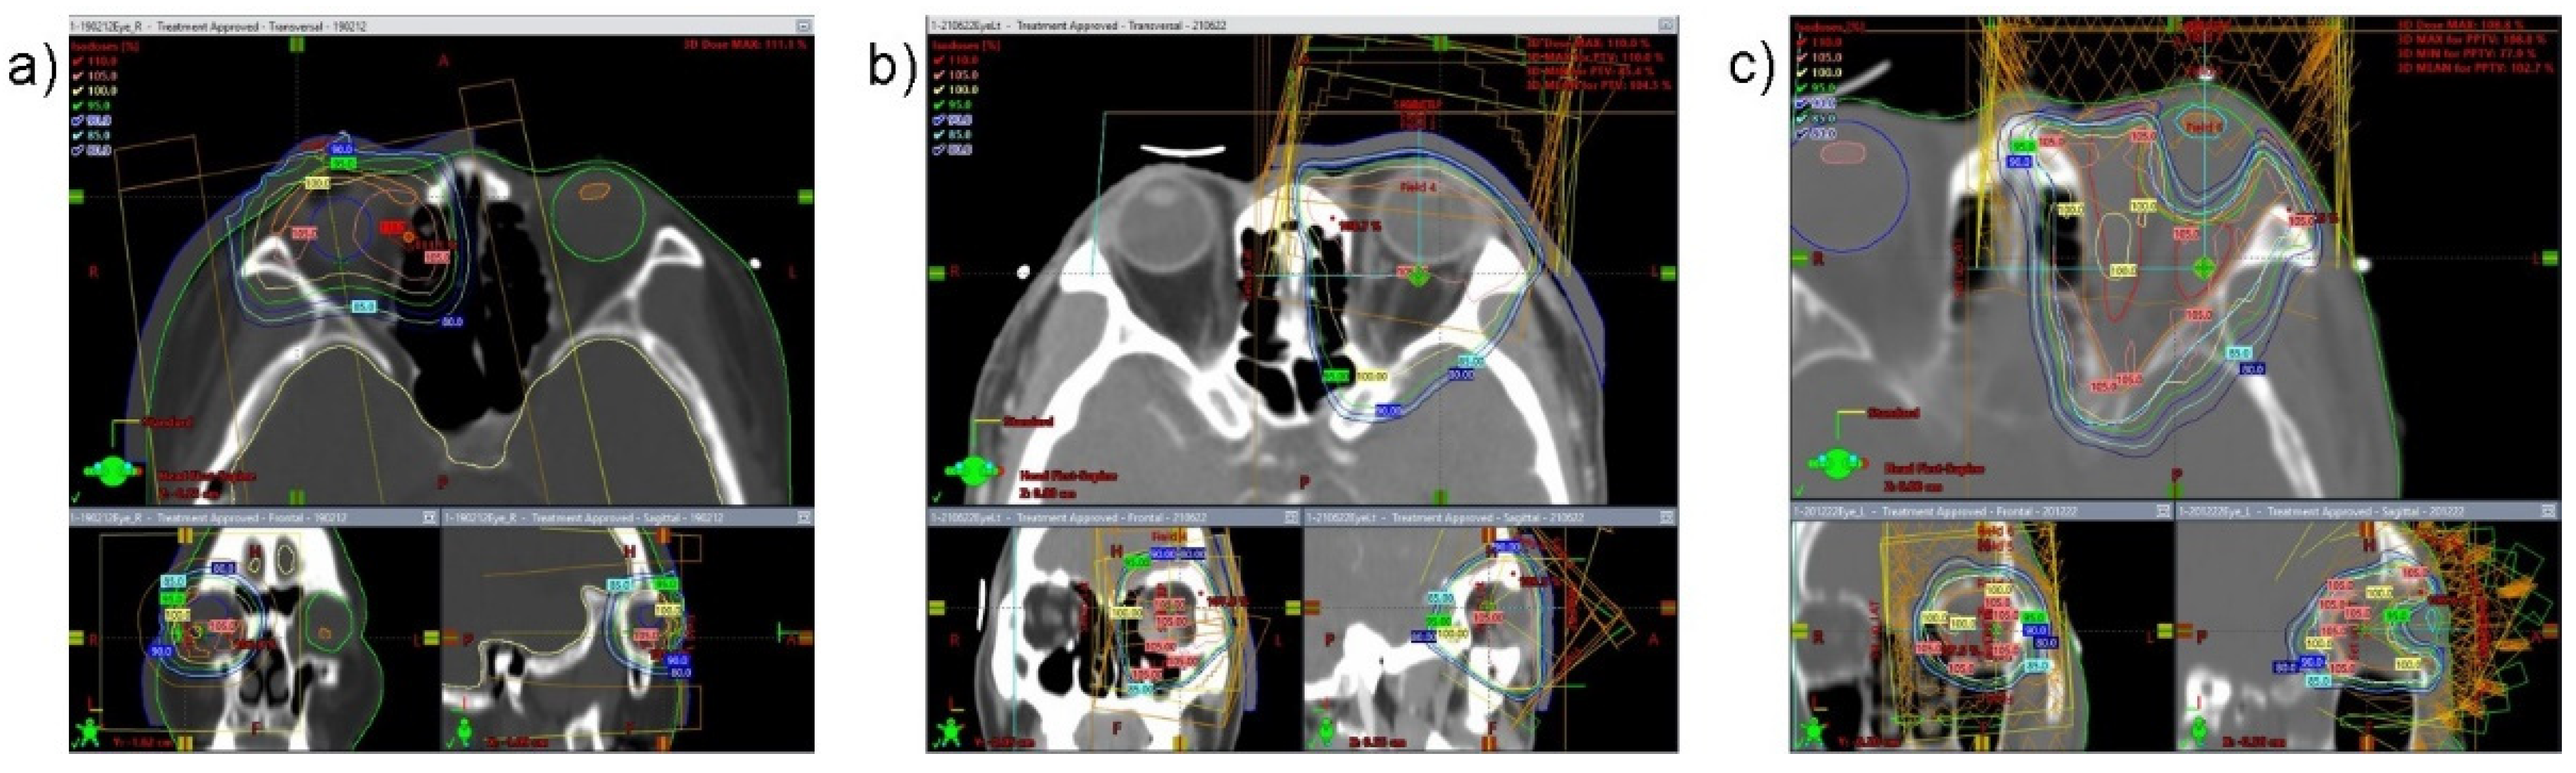

| RT technique | ||

| 2D | 14 | 82.3 |

| 3D | 2 | 11.8 |

| IMRT | 1 | 5.9 |